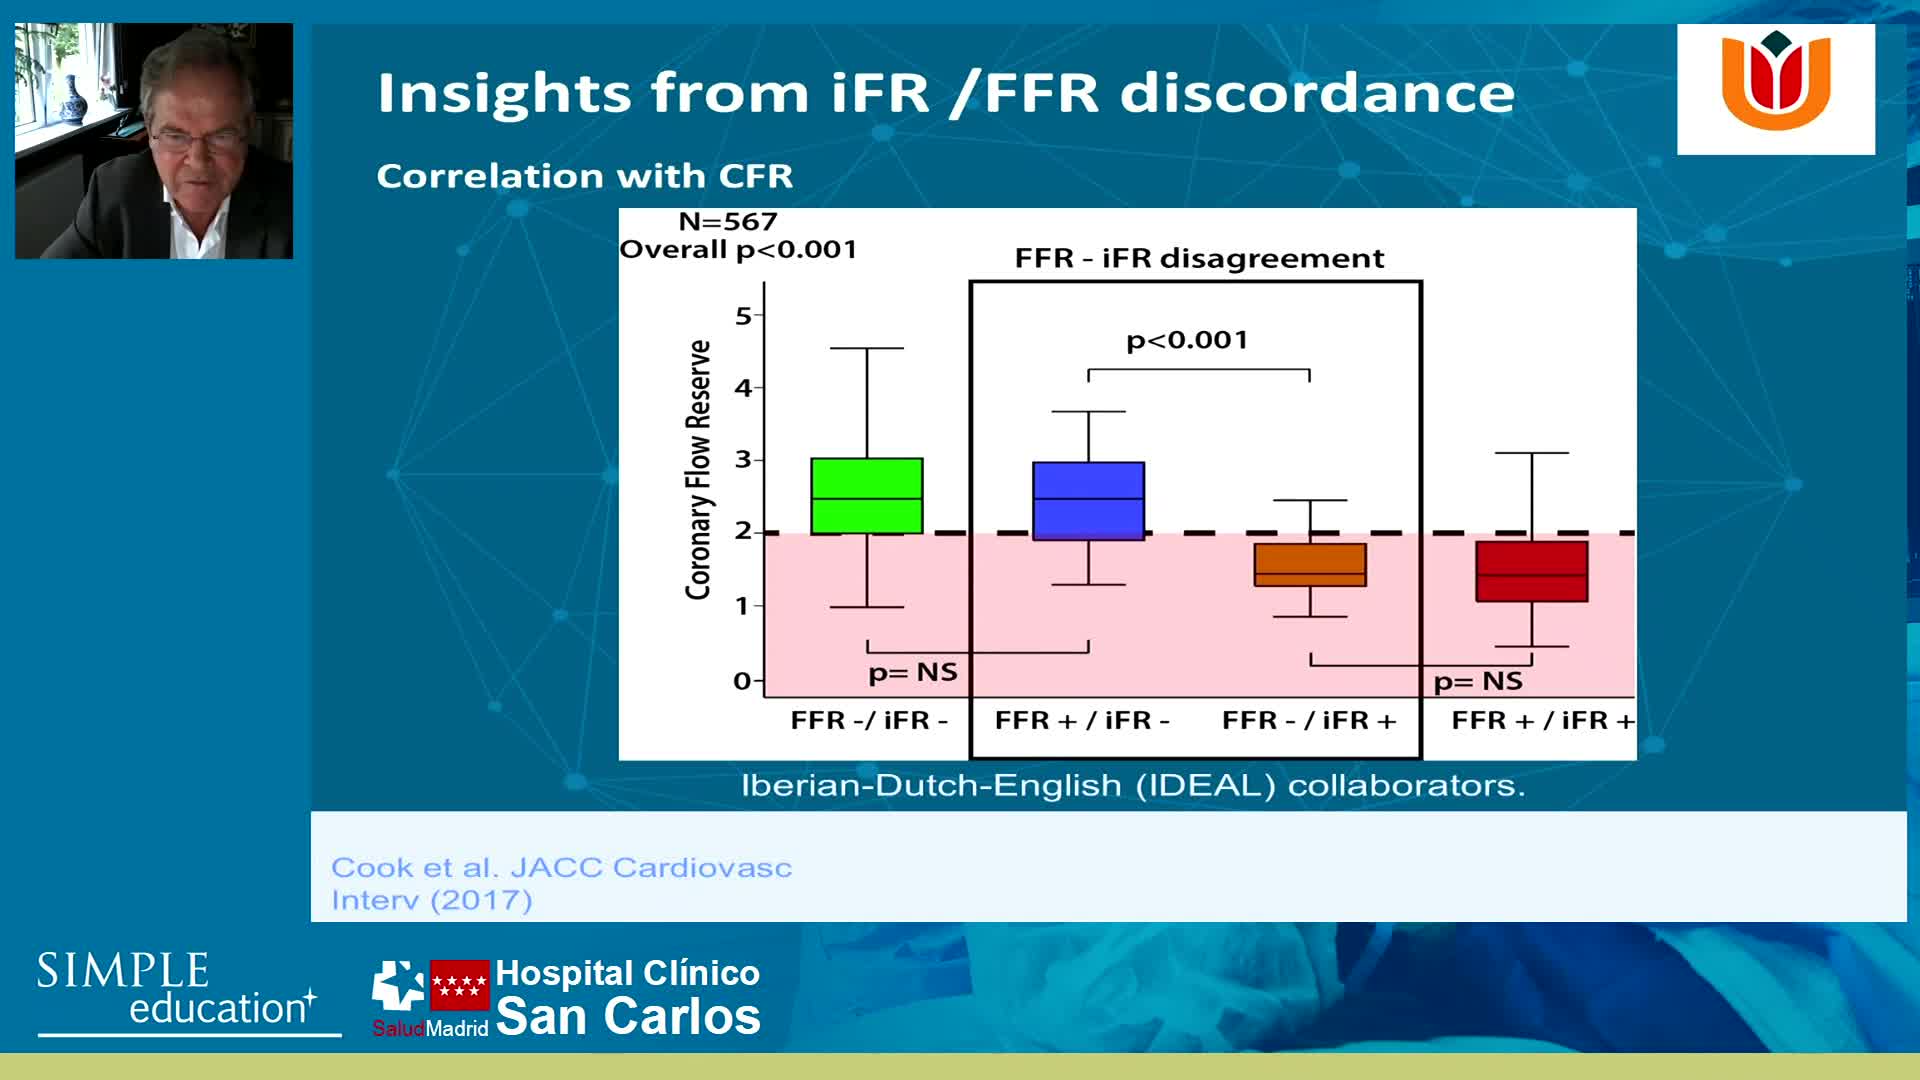

Why is the physiology negative? Integration of the coronary microcirculation to decision-making

Understanding mechanisms of regulation of resting and hyperaemic blood flow, across single and serial stenoses

20 year overview of clinical trial data to support the use of coronary physiology in revascularisation decision-making